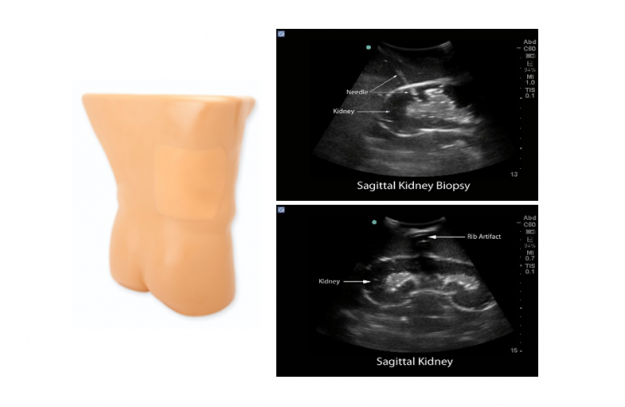

[PC-BPE022] 콩팥생검 초음파 팬텀

피부, 갈비뼈, 오른쪽 신장 및 인접 장기의 초음파로 표현

신장 초음파 검사 방법, 천자 위치 파악, 천자 경로 선택, 천자 시술 중 손-협응, 초음파 유도 경피적 신장 조직 검사, 신장 종양 절제술을 위한 실습에 적합

- 신피질, 신수질, 주요 및 경미한 석회암과 같은 내부 신장 구조에 대한 보기를 제공